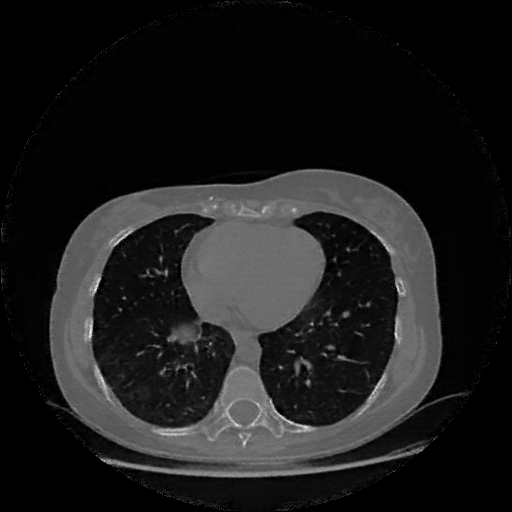

Original VENOUS CT scan

Mediastinum window (WL 40, WW 400 β†’ Low βˆ’160, High +240)